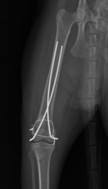

Chirurgia, ortopedia

Wykonujemy szereg zabiegów operacyjnych z zakresu chirurgii miękkiej, jak i twardej. Przeprowadzane przez nas operacje często ratują życie, a niejednokrotnie również polepszają jego jakość.

W przeciwieństwie do wielu gabinetów nasz zespół operuje w składzie 3-osobowym. Jest to niezmiernie ważne, ponieważ ułatwia chirurgowi pracę oraz znacznie skraca czas wykonywania operacji. Dla pacjenta jest to wyznacznikiem profesjonalnie i bezpiecznie wykonanego zabiegu.

Zapewniamy stały nadzór anestezjologiczny i monitoring pacjenta podczas zabiegu oraz opiekę pooperacyjną.

W ramach chirurgii twardej przeprowadzamy m.in. takie zabiegi jak:

• operacyjne leczenie złamań i zwichnięć